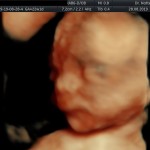

Modalidad de imagen ecográfica que permite evaluar, medir y capturar estructuras fetales superficiales e internas en 3 dimensiones (3D) y también en movimiento y en tiempo real (4D) con programas de realismo aumentado (HD LIVE) e imágenes tomografías fetales (TUI) mejorando significativamente la precisión en las mediciones fetales y la documentaciones de estructuras anatómicas.

Esta tecnología se puede utilizar desde la 6ta a la 40ma semana de embarazo.